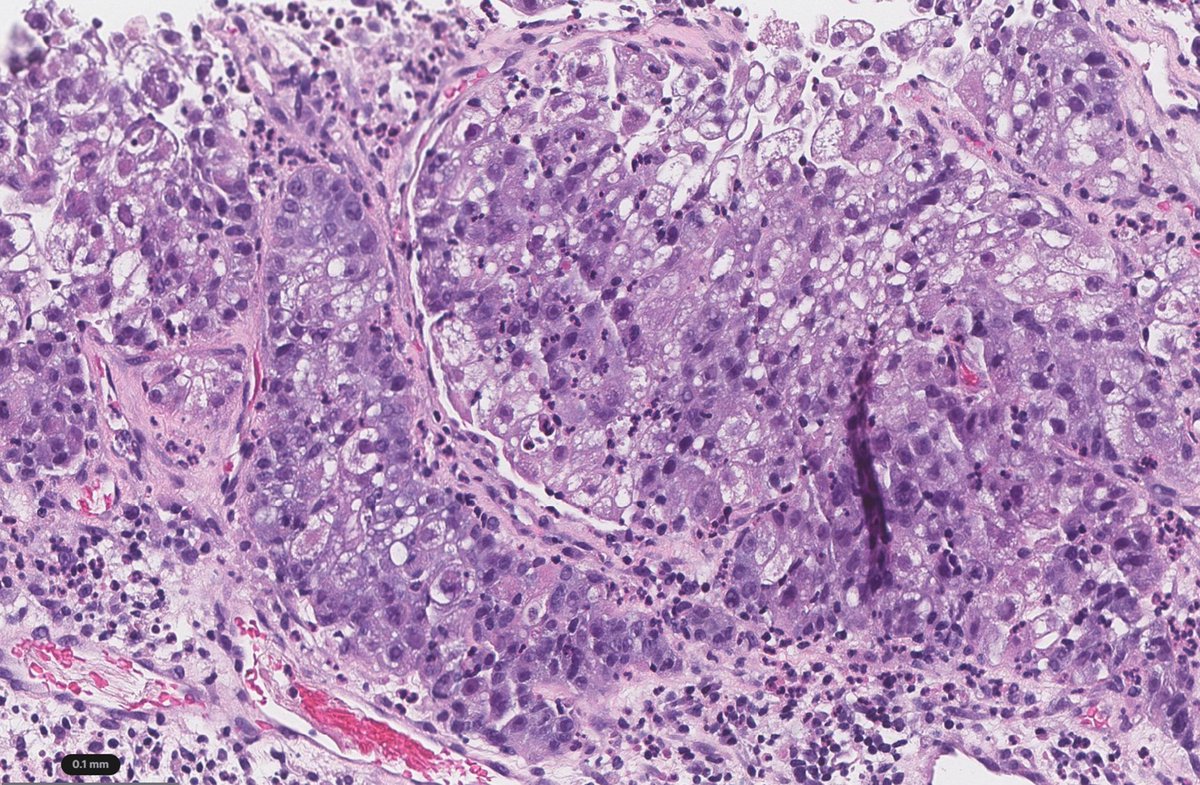

🧬✨ POLE-mutated endometrial cancer → ultramutated biology & excellent survival 🌟